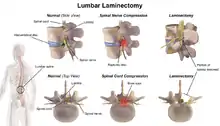

A laminectomy is a surgical procedure that removes a portion of a vertebra called the lamina, which is the roof of the spinal canal. It is a major spine operation with residual scar tissue and may result in postlaminectomy syndrome. Depending on the problem, more conservative treatments (e.g., small endoscopic procedures, without bone removal) may be viable.[1]

The lamina is a posterior arch of the vertebral bone lying between the spinous process (which juts out in the middle) and the more lateral pedicles and the transverse processes of each vertebra. The pair of laminae, along with the spinous process, make up the posterior wall of the bony spinal canal. Although the literal meaning of laminectomy is 'excision of the lamina', a conventional laminectomy in neurosurgery and orthopedics involves excision of the supraspinous ligament and some or all of the spinous process. Removal of these structures with an open technique requires disconnecting the many muscles of the back attached to them. A laminectomy performed as a minimal spinal surgery procedure is a tissue-preserving surgery that leaves more of the muscle intact and spares the spinal process. Another procedure, called the laminotomy, is the removal of a mid-portion of one lamina and may be done either with a conventional open technique or in a minimalistic fashion with the use of tubular retractors and endoscopes.

The reason for lamina removal is rarely, if ever, because the lamina itself is diseased; rather, it is done to break the continuity of the rigid ring of the spinal canal to allow the soft tissues within the canal to: 1) expand (decompress); 2) change the contour of the vertebral column; or 3) permit access to deeper tissue inside the spinal canal. A laminectomy is also the name of a spinal operation that conventionally includes the removal of one or both lamina, as well as other posterior supporting structures of the vertebral column, including ligaments and additional bone. The actual bone removal may be carried out with a variety of surgical tools, including drills, rongeurs and lasers.

The success rate of a laminectomy depends on the specific reason for the operation, as well as proper patient selection and the surgeon's technical ability. The first laminectomy was performed in 1887 by Victor Alexander Haden Horsley,[2] a professor of surgery at University College London. A laminectomy can treat severe spinal stenosis by relieving pressure on the spinal cord or nerve roots, provide access to a tumor or other mass lying in or around the spinal cord, or help in tailoring the contour of the vertebral column to correct a spinal deformity such as kyphosis. A common type of laminectomy is performed to permit the removal or reshaping of a spinal disc as part of a lumbar discectomy. This is a treatment for a herniated, bulging, or degenerated disc.

For spinal stenosis

Most commonly, a laminectomy is performed to treat spinal stenosis. Spinal stenosis is the single most common diagnosis that leads to spinal surgery, of which a laminectomy represents one component. The lamina of the vertebra is removed or trimmed to widen the spinal canal and create more space for the spinal nerves and thecal sac. Surgical treatment that includes a laminectomy is the most effective remedy for severe spinal stenosis; however, most cases of spinal stenosis are not severe enough to require surgery. When the disabling symptoms of spinal stenosis are primarily neurogenic claudication and the laminectomy is done without spinal fusion, there is generally a more rapid recovery with less blood loss.[3] However, if the spinal column is unstable and fusion is required, the recovery period can last from several months to more than a year, and the likelihood of symptom relief is far less probable.[4]